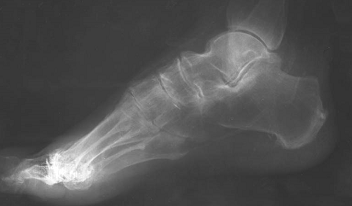

Рис.

6. Сенильный остеопороз стопы.